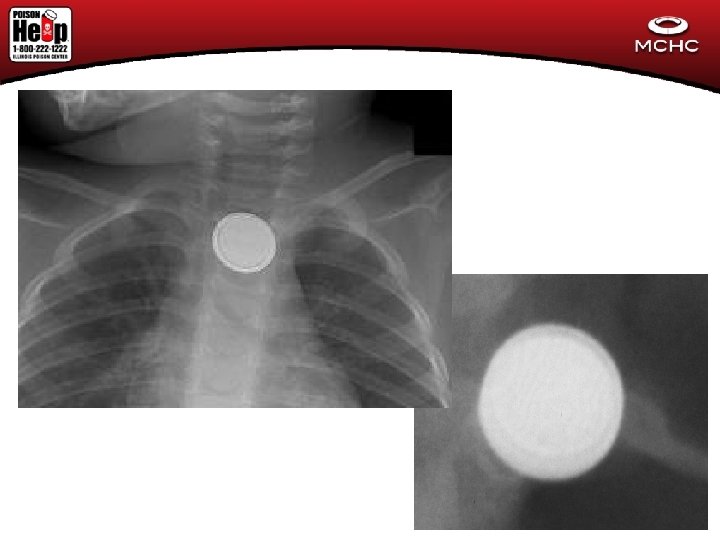

Case #1 (Christmas Tox) • 18 month old child thought to have a respiratory infection (cough and vomiting) by family comes to ED for evaluaton. • CXR shows FB in esophagus

Button Battery # 2 • 4 yo female found pulseless and apneic with blood around mouth and nares • Initially thought to be trauma • CXR with Foreign Body in esophagus

Button Battery Case #3 • 4 yo cough for over a week. May have been treated with acetaminophen. • CXR showed a 20 mm disc in esophagus

Button Battery Case #1 • Time delay in transfer to appropriate facility • Both batteries removed endoscopically • Admitted for 4 days. Barium swallow with undefined esophageal deviation • Discharged with fever on abx and medication for acid reflux • 4 days later found cyanotic and in shock • Death Certificate with aorto-esophageal ulcer/fistula

Button Battery # 2 • 4 yo female found pulseless and apneic with blood around mouth and nares • Initially thought to be trauma • CXR with button battery in esophagus Rest of Story • Taken to operating room • Unable to resuscitate • Intra-operative finding?

Button Battery Case #3 • 4 yo cough for over a week. May have been treated with acetaminophen. • CXR showed a 20 mm disc in esophagus Rest of Story: • Transferred to tertiary care center, removed endoscopically • Admitted to ICU • Developed massive GI bleed, liver failure, renal failure • Child arrested during exploratory laparoscopy

Button Batteries • • Fatal in rare cases Over 5, 500 ED visits in 2009 Larger, newer batteries most often implicated Burns can occur in 2 to 2. 5 hours